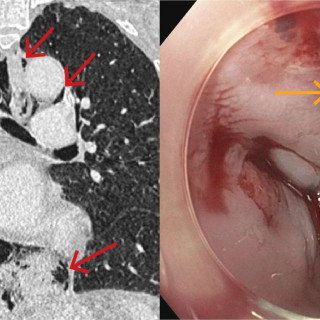

Denne kasuistikken beskriver alvorlig iatrogen botulisme etter behandling med injeksjon av botulinumtoksin ved en privatklinikk i utlandet. En kvinne i 40-årene ble akuttinnlagt i medisinsk avdeling grunnet økende svelgparese, svakhet i nakkemuskulatur, obstipasjon, munntørrhet, hodepine, fatigue, tunge øyelokk og uklart syn de siste fem dager. De siste tre dagene før innleggelsen hadde hun ikke fått i seg flytende eller fast føde, og hodet måtte støttes når hun skulle sette seg opp. Det fremkom at hun 15 dager tidligere hadde fått injisert botulinumtoksin type A mot migreneplager under et...